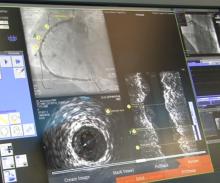

W. L. Gore & Associates Inc. has received U.S. Food and Drug Administraion (FDA) approval for the new large diameter 35 mm trunk-ipsilateral leg and 36 mm aortic extender components, as well as the lower profile 31 mm diameter trunk-ipsilateral leg and 32 mm aortic extender components of the Gore Excluder AAA Endoprosthesis. The new components provide physicians with a proven and durable endovascular option to treat abdominal aortic aneurysms (AAAs).